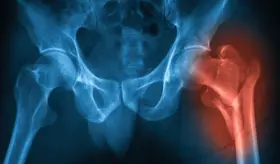

Su síntoma principal es el dolor en la ingle que puede irradiar al abd...